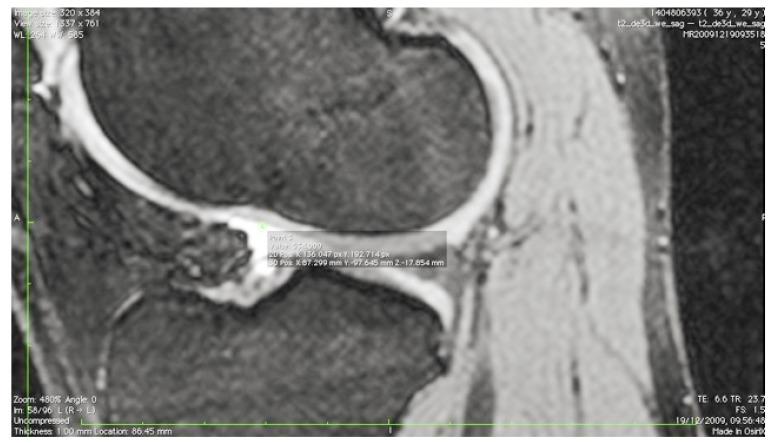

The guide design was based on MRI scan of the subject's uninjured contralateral knee, identifying the femoral footprint and its anatomical position relative to the borders of the femoral articular cartilage. Image processing software was used to create a 3D computer aided design which was subsequently exported to a 3D-printing service.

导向器设计基于受试者未受伤对侧膝关节的磁共振成像扫描,确定股骨足迹及其相对于股骨关节软骨边界的解剖位置。使用图像处理软件创建三维计算机辅助设计,随后将其导出至三维打印服务。